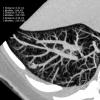

This pictorial review is based on our experience of the follow-up of 120 patients at our multidisciplinary center for hereditary hemorrhagic telangiectasia (HHT). Rendu-Osler-Weber disease or HHT is a multiorgan autosomal dominant disorder with high penetrance, characterized by epistaxis, mucocutaneous telangiectasis, and visceral arteriovenous malformations (AVMs). The research on gene mutations is fundamental and family screening by clinical examination, chest X-ray, research of pulmonary shunting, and abdominal color Doppler sonography is absolutely necessary. The angioarchitecture of pulmonary AVMs can be studied by unenhanced multidetector computed tomography; however, all other explorations of liver, digestive bowels, or brain require administration of contrast media. Magnetic resonance angiography is helpful for central nervous system screening, in particular for the spinal cord, but also for pulmonary, hepatic, and pelvic AVMs. Knowledge of the multiorgan involvement of HHT, mechanism of complications, and radiologic findings is fundamental for the correct management of these patients.